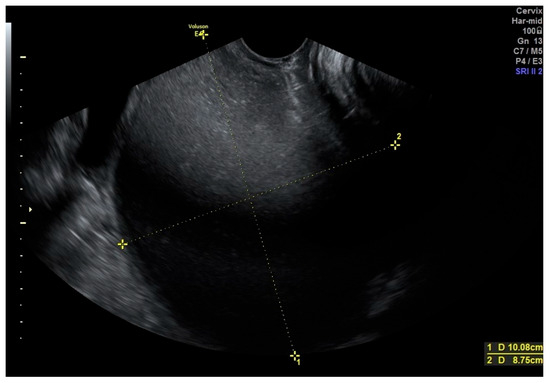

Recurrent Vulvovaginitis as an Unusual Presentation of Diagnosed Obstructed Hemivagina and Ipsilateral Renal Anomalies (OHVIRA) Syndrome in an Adolescent: A Case Report and Review of the Literature

by Ju Seok Yang, Ji Eun Park and Hyen Chul Jo

J. Clin. Med. 2026, 15(2), 440; https://doi.org/10.3390/jcm15020440 - 6 Jan 2026

Background: Vulvovaginitis is a common condition in pediatric and adolescent female patients and is most frequently caused by infection. Although non-infectious etiologies are less common, they should be considered, particularly in cases that are refractory to standard treatment. Case: We report a rare [...] Read more.

Background: Vulvovaginitis is a common condition in pediatric and adolescent female patients and is most frequently caused by infection. Although non-infectious etiologies are less common, they should be considered, particularly in cases that are refractory to standard treatment. Case: We report a rare case of a 16-year-old adolescent who was ultimately diagnosed with obstructed hemivagina and ipsilateral renal anomalies (OHVIRA) syndrome after experiencing recurrent vulvovaginitis for more than one year. Despite repeated antimicrobial treatments, her symptoms persisted. Further imaging studies revealed uterine didelphys with an obstructed hemivagina and ipsilateral renal agenesis. Surgical resection of the vaginal septum resulted in complete resolution of symptoms. Conclusions: Müllerian anomalies, such as OHVIRA syndrome, should be considered in the differential diagnosis for adolescents with recurrent vulvovaginitis refractory to conventional therapy. Delayed diagnosis may result in complications that significantly impair both quality of life and future reproductive potential. Full article